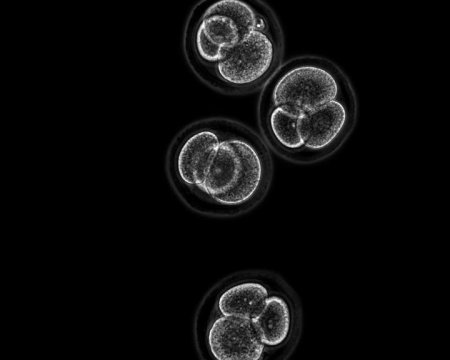

Researchers at the Hebrew University of Jerusalem (HU) have found a way to transform skin cells into the three major stem cell types that comprise early-stage embryos. The work (in mouse cells) has significant implications for modelling embryonic disease and placental dysfunctions, as well as paving the way to create whole embryos from skin cells.

As published in Cell Stem Cell, Dr. Yossi Buganim of HU’s Department of Developmental Biology and Cancer Research and his team discovered a set of genes capable of transforming murine skin cells into all three of the cell types that comprise the early embryo: the embryo itself, the placenta and the extra-embryonic tissues, such as the umbilical cord. In the future, it may be possible to create entire human embryos out of human skin cells, without the need for sperm or eggs. This discovery also has vast implications for modelling embryonic defects and shedding light on placental dysfunctions, as well as solving certain infertility problems by creating human embryos in a petri dish.

Now, the Hebrew University research team, headed by Dr. Yossi Buganim, Dr. Oren Ram from the HU’s Institute of Life Science and Professor Tommy Kaplan from HU’s School of Computer Science and Engineering, as well as doctoral students Hani Benchetrit and Mohammad Jaber, found a new combination of five genes that, when inserted into skin cells, reprogram the cells into each of three early embryonic cell types — iPS cells which create fetuses, placental stem cells, and stem cells that develop into other extra-embryonic tissues, such as the umbilical cord. These transformations take about one month.

Recently, attempts have been made to develop an entire mouse embryo without using sperm or egg cells. These attempts used the three early cell types isolated directly from a live, developing embryo. However, HU’s study is the first attempt to create all three main cell lineages at once from skin cells. Further, these findings mean there may be no need to “sacrifice” a live embryo to create a test tube embryo.